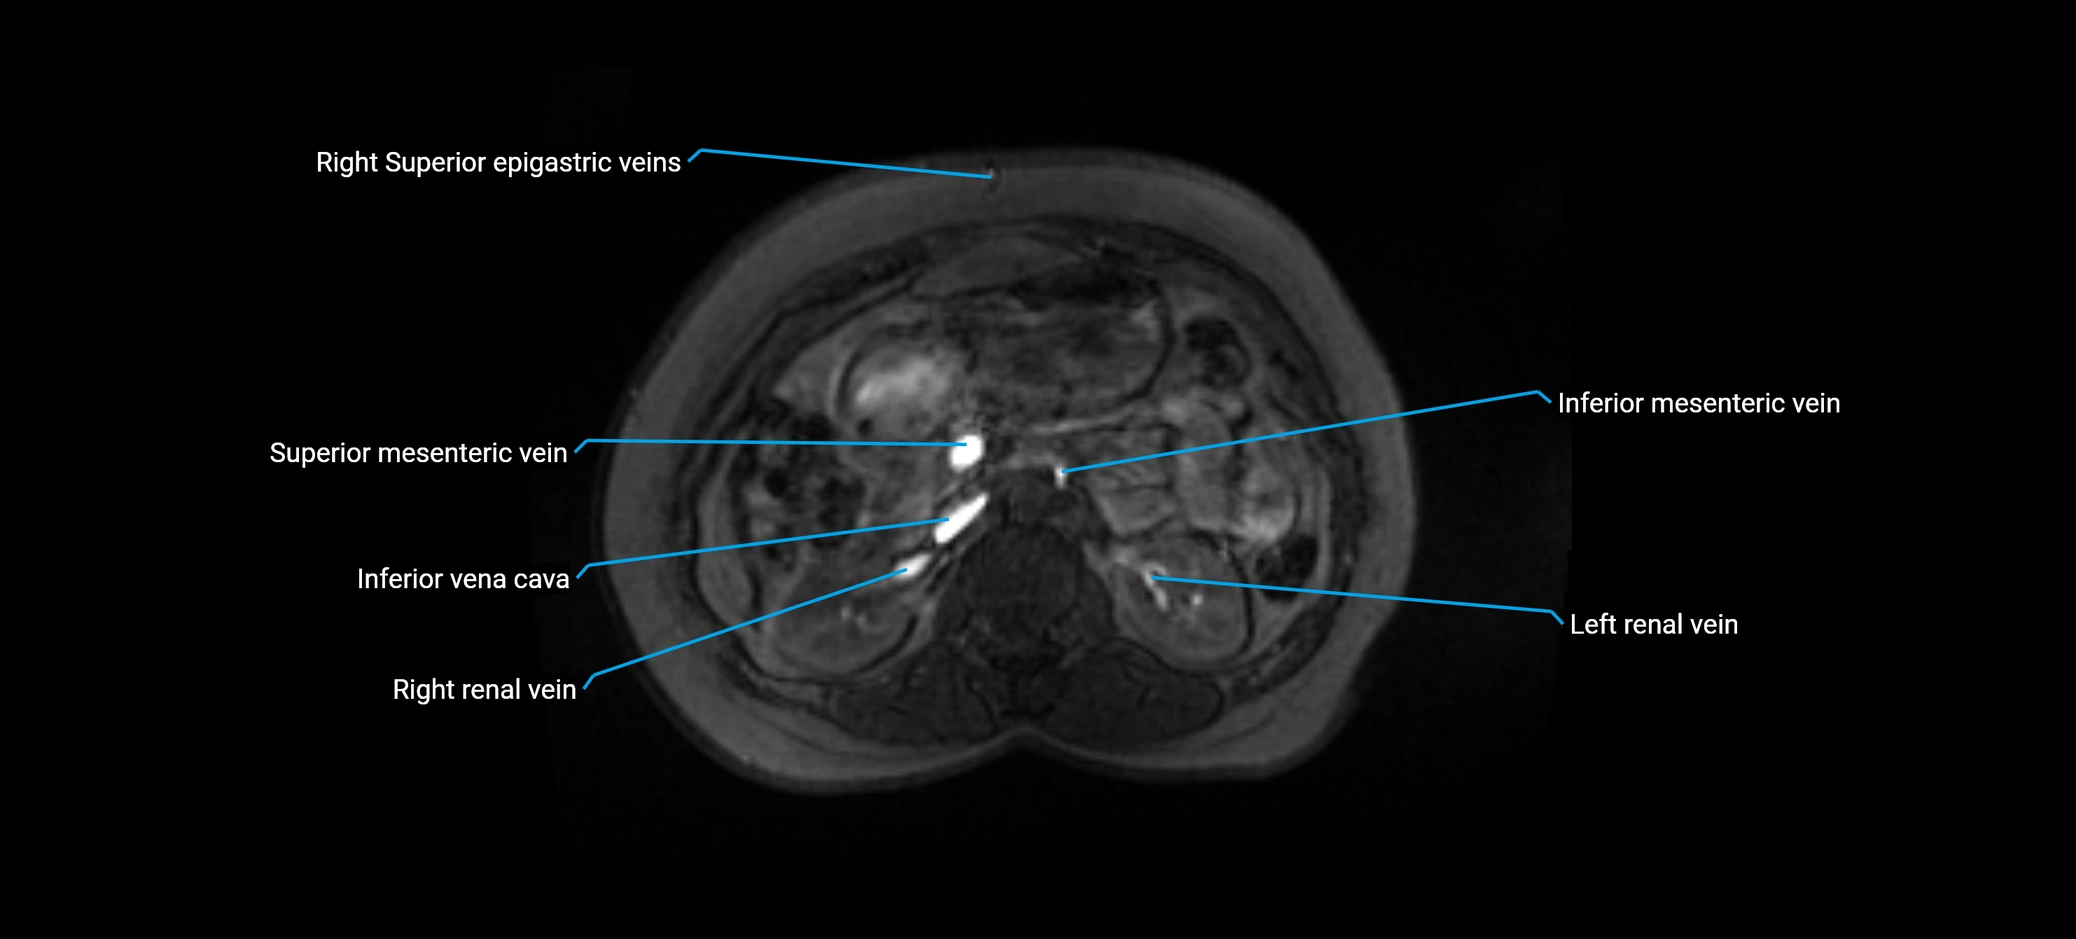

MRI image

image